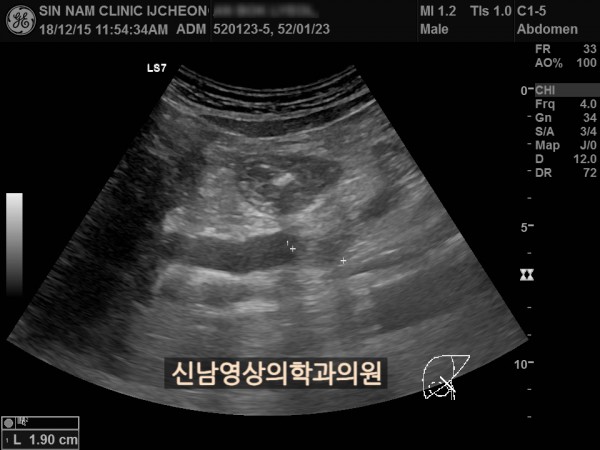

상복부 초음파 적용 사례

본 환자분은 50대 중반의 남성분으로 손가락안이 가렵다는 느낌으로 내원하셨습니다.

담도암과 담관암은 같은 질환을 지칭하는 용어로 간에서 만들어진 담즙이 십이지장으로 이동하는 통로인 담관에 발생하는 악성 종양입니다.

이 암은 간 안에 생기는 간내 담관암과 간 바깥에 생기는 간외 담관암으로 나뉘며, 가장 흔한 증상으로 통증이 없는 황달, 짙은 소변, 옅은 변, 복통, 체중 감소, 소양증 등이 나타날 수 있습니다.

치료는 암의 위치와 진행 정도에 따라 수술, 항암 치료, 담관 스텐트 삽입 등으로 이루어집니다.

담관암의 정확한 원인은 아직 밝혀지지 않았지만 담관 내 만성 염증, 담관 결석, 경화성 담관염, 간디스토마(간흡충증), 염증성 대장 질환 등이 관련 있는 것으로 알려져 있습니다.